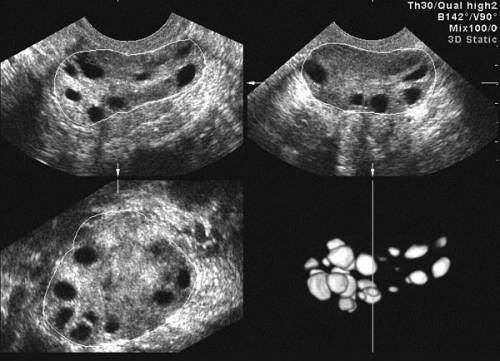

Диагностика

Для того чтобы выяснить, как правильно лечить поликистоз яичников с целью зачатия, женщине необходимо пройти ряд диагностических процедур. Следующие методы исследования помогут оценить вероятность наступления беременности:

Ультразвуковое исследование органов малого таза с акцентом на состояние яичников.

Магнитно-резонансная томография (МРТ), которая позволяет изучить анатомию, расположение и уровень кровоснабжения яичников.